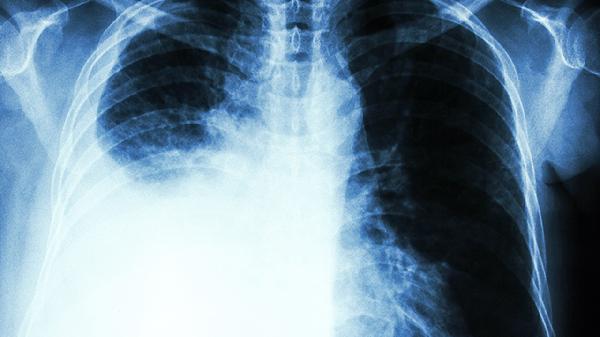

4、放疗后肺损伤

胸部肿瘤放疗后常见放射性肺损伤,表现为干咳、胸痛、气短等症状。养阴清肺膏可通过滋养肺阴减轻放疗引起的燥热伤阴,所含牡丹皮具有抗纤维化作用。需配合胸部CT评估肺纤维化程度,严重者需联合糖皮质激素治疗。